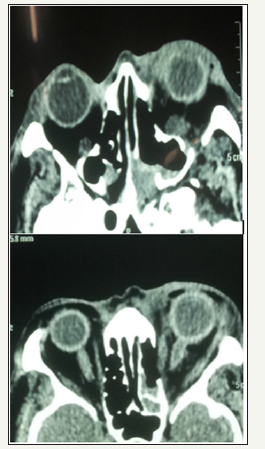

Figure 2:CT scan findings showing significant orbital inflammation (Note the globe is visible on the right, but not on the leftindicating proptosis), on the left showing limited lamina papyracea disease.

Figure 4:Patient of IFS, after debridement, showing residual disease posteriorly, which is difficult to treat (top) and enhancement of the medial rectus (Bottom).